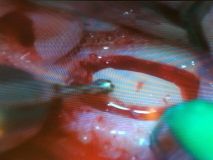

دوره آموزشي سينوس ليفت همراه با جراحي زنده

تاريخ: ٨-٩ بهمن ١٣٩٤

اساتيد:

دكتر كريمي

دكتر مشير آبادي

دكتر خليلي

دكتر عميد